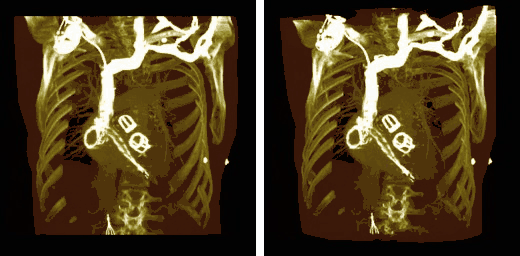

The final image processing step is to volume render this difference stack along with the "pure perfusion" scan and to blend the results, as illustrated in the following image:

subFusion processing applied to a SPECT lung ventilation-perfusion scan: Both lungs of the patient displayed on the left, with their right lung displayed in the top right and their left lung below it. The "pure perfusion" scan is displayed using a grey-scale and the difference data using a spectrum CLUT, where large differences are coded in red with intermediate differences in yellow and smaller differences in green.

The steps involved are outlined in the following diagram. Note that minor processes, such as CLUT selection, relative opacity adjustment and contrast enhancement are omitted from this diagram for the sake of simplicity. Note also that an image registration step may need inclusion at the beginning of the procedure in cases where patient movement occurs between the two SPECT acquisitions.

Block diagram of the 3D subFusion process.

A final point to note is the larger appearance of the patient's lungs in the segmented CTPA images relative to the SPECT images. This arises because the CTPA study was acquired using a single breath-hold and the SPECT studies with the patient breathing quietly over the period of gamma camera rotation. The spatial registration of the three sets of images is therefore not possible directly, and would require the application of spatial warping and other techniques which, unfortunately, are beyond the scope of our treatment here.